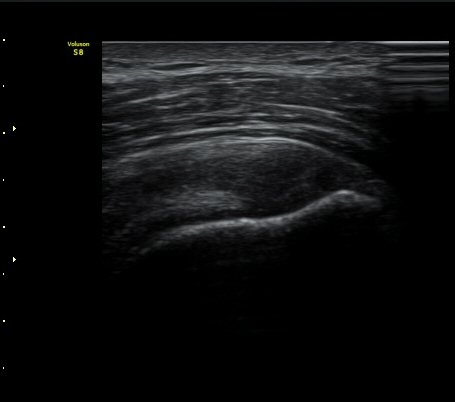

°ß°©ÇÏ±Ù°Ç ÁߺΠȾ´Ü¸é°Ë»ç»ó °ß°©Çã±Ù°ÇÀÌ ¾ã¾ÆÁö°í Á¡¾×³¶³» ¼ö¾×Àú·ù°¡ °üÂûµÊ

(±×¸² 8, 9).